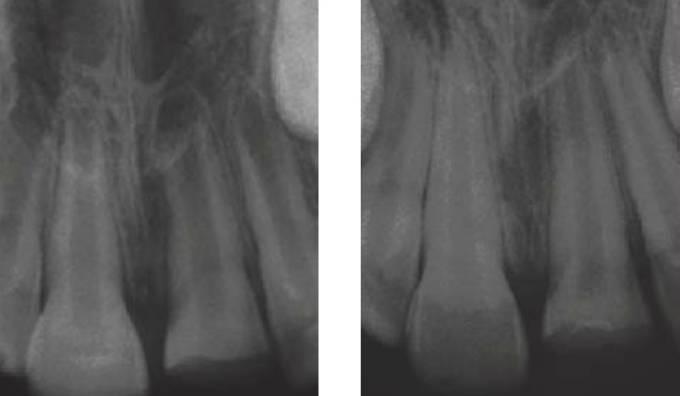

Radiografías

Por supuesto, tras el minucioso estudio se solicitarán radiografías. Las radiografías extraorales son de gran utilidad en niños pequeños, por ejemplo, radiografías panorámicas, ya que en los casos de niños muy alterados o difíciles puede resultar la única forma de obtener cierta información clínica en la fase aguda de tratamiento.

En el caso de las radiografías periapicales, deberán tomarse varias proyecciones de cada uno de los dientes traumatizados para determinar con exactitud la presencia de fracturas de raíz y luxaciones dentales. Como base, deben obtenerse radiografías de todos los dientes que han sufrido un traumatismo a fin de evaluar:

Para comprobar la existencia de fracturas radiculares horizontales, se deberá cambiar la angulación vertical de las radiografías periapicales y, cuando se examinan fracturas radiculares verticales, se deberá cambiar la angulación horizontal.

En ocasiones, no se evidencia en un principio una fractura radicular horizontal, ya que el lugar de la fractura se abre bajo la influencia de un exudado inflamatorio varios días después de la lesión. Por tanto, en todo diente traumatizado se debe repetir la radiografía a las 2 semanas (fig. 7.24).